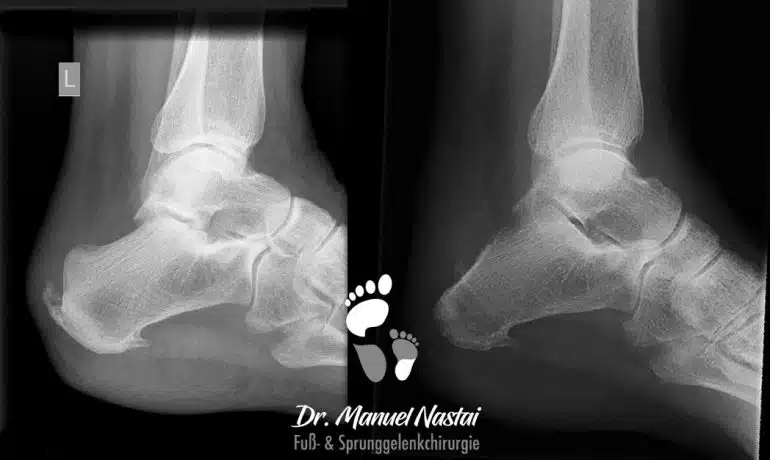

Minimalinvasive Haglund-Exostosenresektion

Die Haglund-Ferse ist eine häufige Ursache von Fersenschmerzen. Patienten klagen über erhebliche belastungs- und bewegungsabhängige Schmerzen im Bereich des Achillessehnenansatzes. Grund ist eine besondere Form...

Offene Kalkaneoplastik

Die offene Kalkaneoplastik ist eine Methode zur operativen Behandlung der Haglundferse mit hinterem Fersensporn und Verkalkungen in der Struktur der Achillessehne. Diese Verkalkungen entstehen nach...